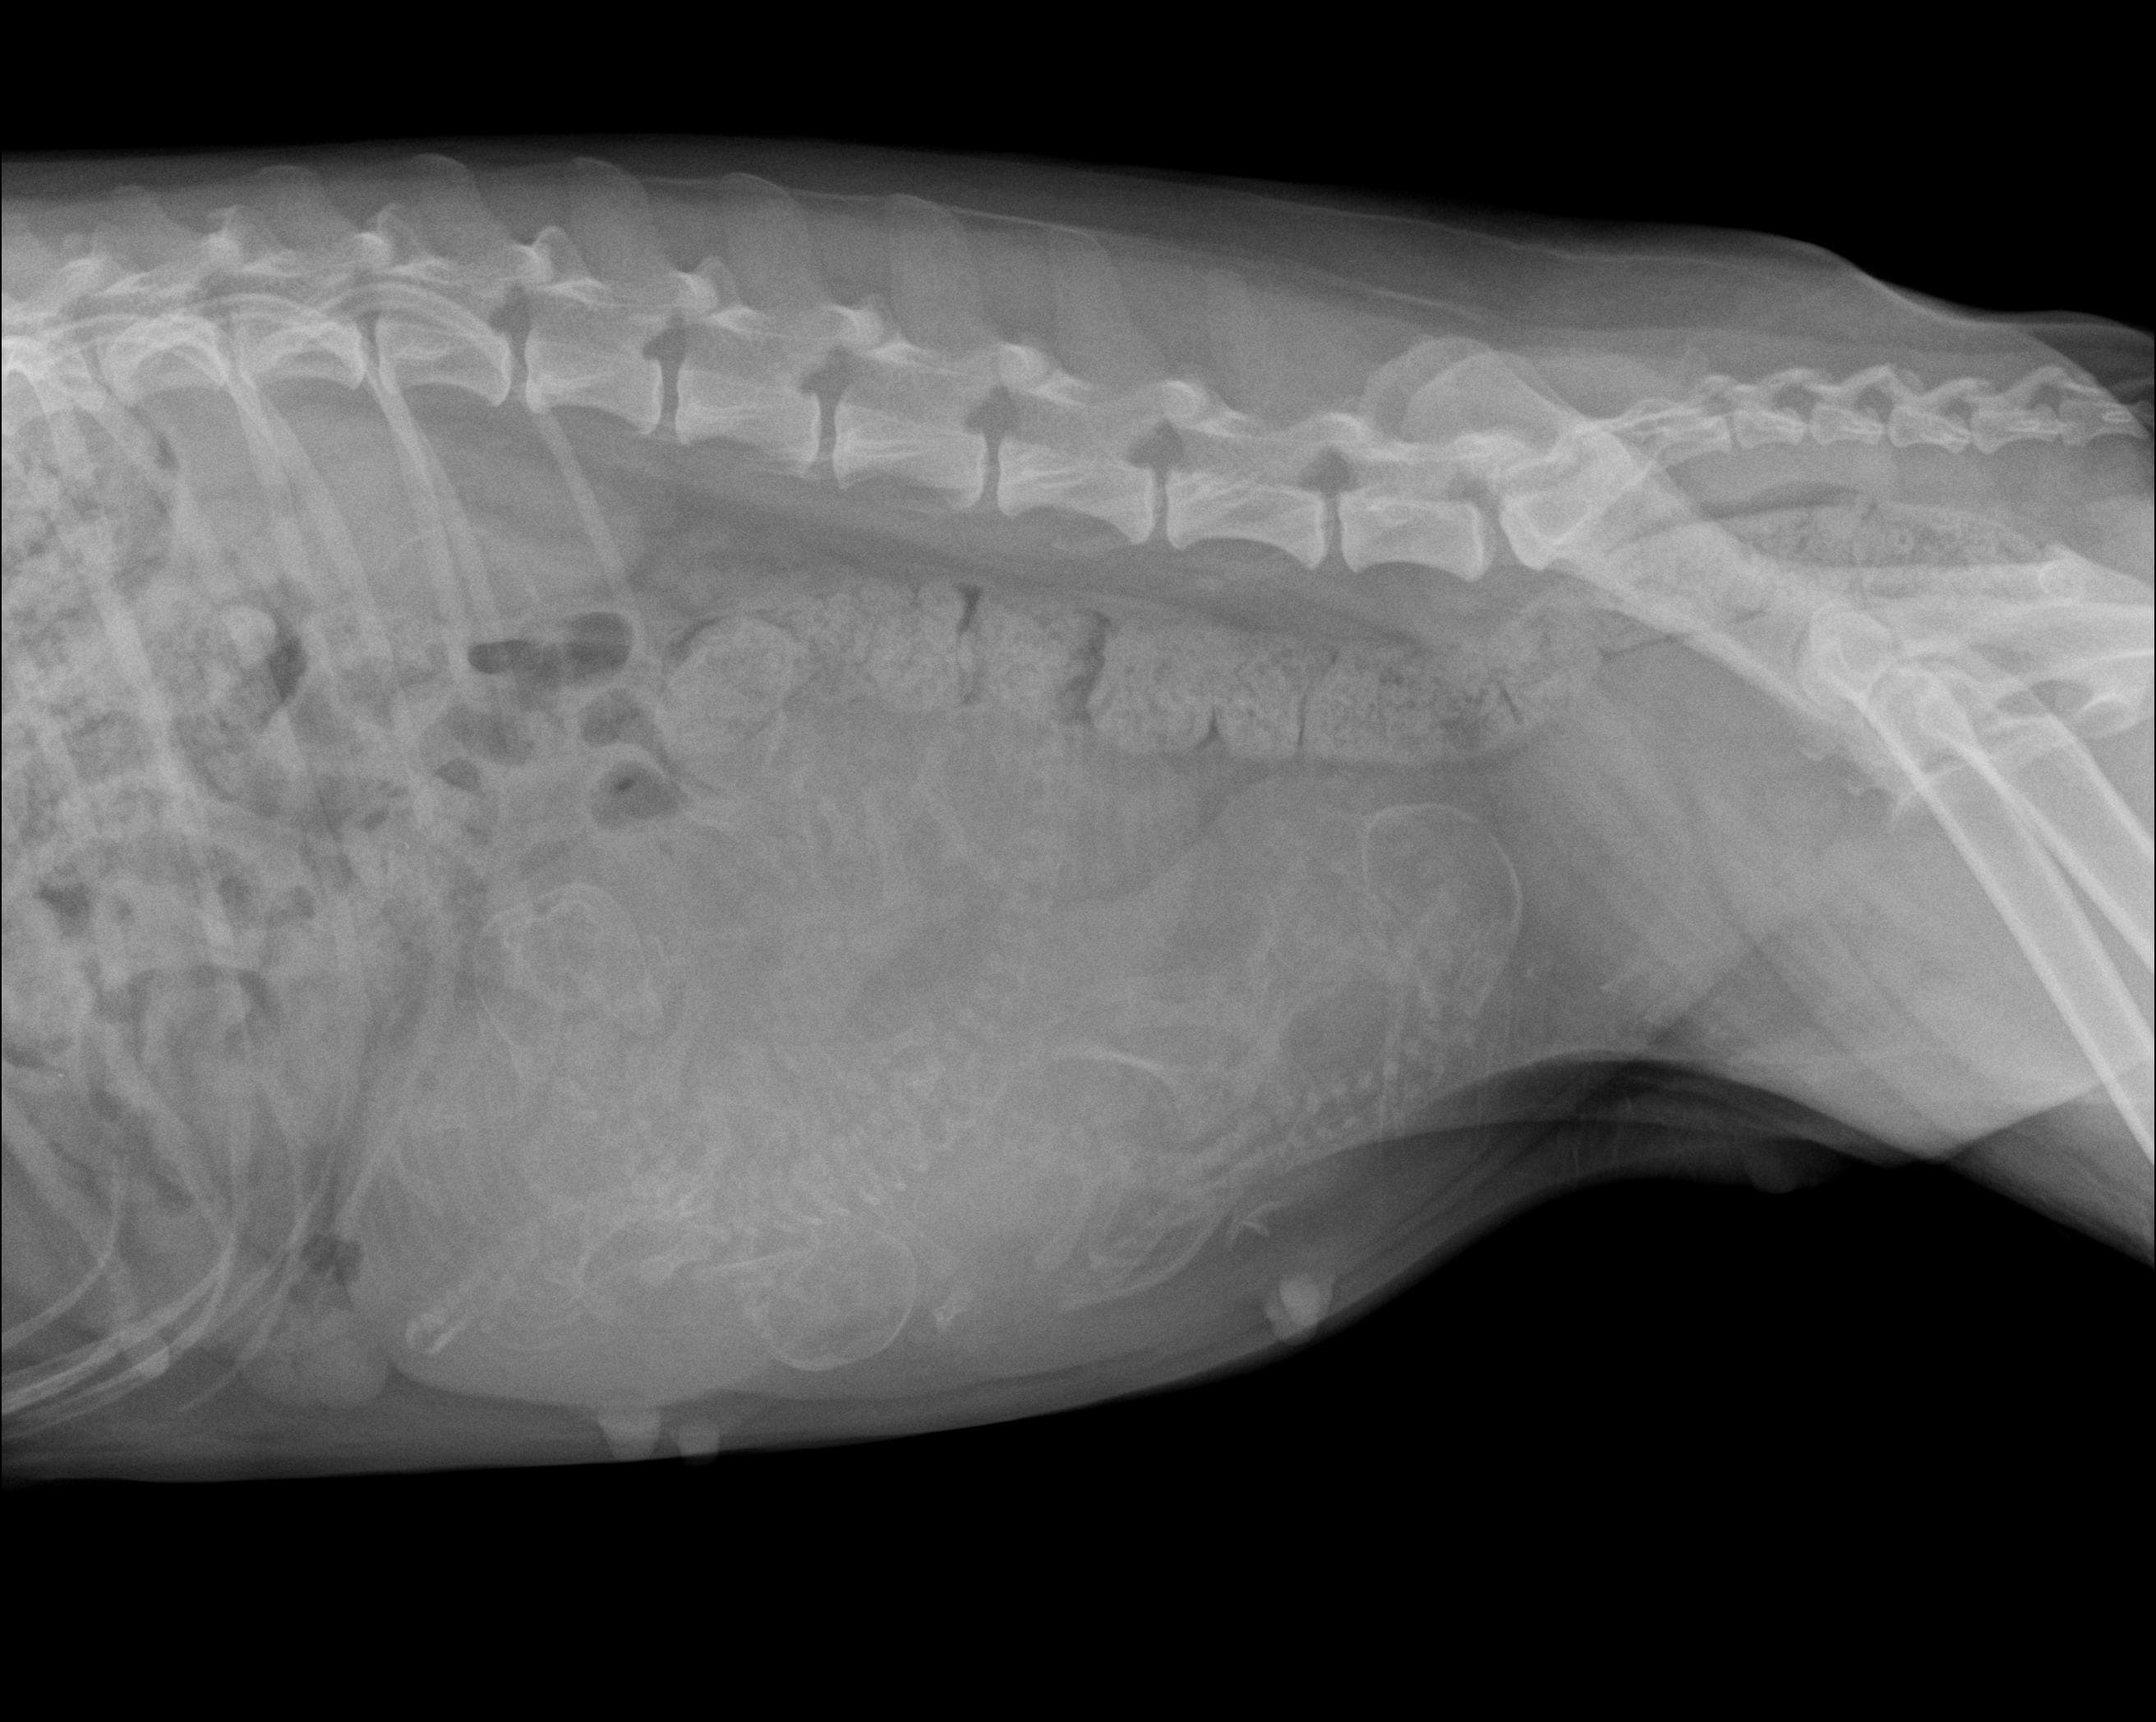

Nosso serviço de radiologia digital é projetado para oferecer diagnósticos precisos para cuidar da saúde dos pets. Contamos com equipamentos de última geração que nos permitem capturar imagens de alta qualidade e definição, fornecendo uma visão clara das estruturas. Essa tecnologia avançada nos permite identificar diversas condições médicas com maior precisão e detalhamento.